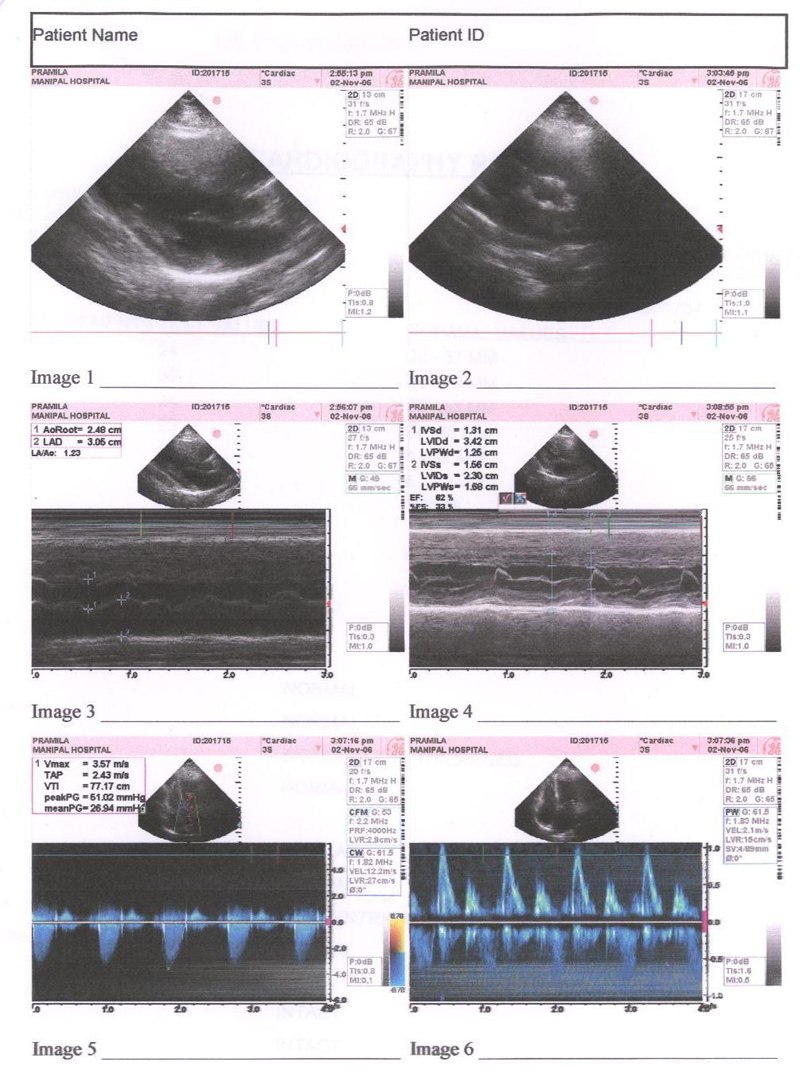

The Echocardiography done on 2nd Nov. 2006 done on Manipal Hospital clearly states Bicuspid and Thickened Aortic Valve, Mild Aortic Stenosis, Concentric LV Hyper trophy. But patient condition from 2nd Nov. to 2nd DEC had already deteriorated and she was supposed to be admitted in the Hospital By 15 th DEC. 2006

The Echocardiography report of 2nd Nov. 2006 is shown in fig 1

FIG 1:- Echocardiography report of 2nd Nov. 2006